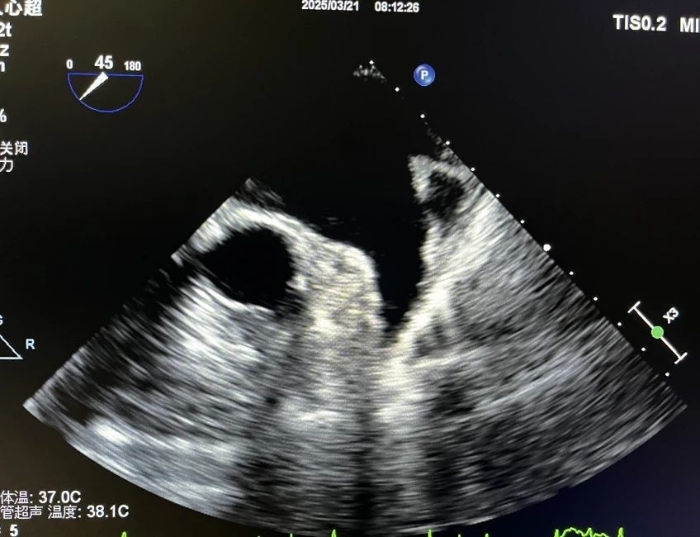

直擊“醫”線|我院成功開展首例TEE引導下房顫射頻消融術前評估

近日,我院超聲科聯合心血管病院房顫中心成功實施首例經食道超聲心動圖(TEE),為持續性房顫行經導管消融術開展精準術前評估,標志著我院心內科在復雜心律失常診療領域邁入精準化、微創化新階段,為患者提供了更加安全、高效的一體化診療方案。

超聲科團隊在術前充分溝通后,通過先進設備及精準操作,成功獲取左心房及肺靜脈三維成像,排除了左心耳血栓風險,并精準定位肺靜脈開口,為心血管內科團隊開展手術提供了關鍵影像學依據,保障了手術順利進行。術后,患者生命體征平穩,無相關并發癥。

本病例中,我院超聲科突破傳統檢查局限,有效開展了高難度的經食道超聲心動圖(TEE)引導下房顫消融術前評估;心血管內科團隊精準制定手術方案,實現“影像-治療”無縫銜接,凸顯了我院多學科協作的顯著優勢。

房顫,即心房顫動,是一種常見的心律失常,指心房失去規律的舒張和收縮,代之以無序的顫動,房顫有發生心功能減退、心源性栓塞等風險,且發生的腦栓塞通常致殘率非常高。經導管射頻消融術是持續性房顫的有效治療手段,目前成功率較高。傳統經胸超聲心動圖(TTE)受限于聲窗條件,難以清晰顯示左心房及肺靜脈結構,而經食道超聲心動圖(TEE)通過將探頭置入食管,可近距離、高分辨率觀察心臟細微結構,精準評估左心房血栓、肺靜脈解剖變異等關鍵信息,從而提升手術安全性及成功率。